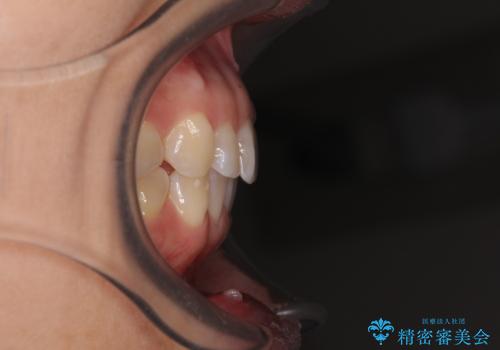

- 上下前歯のデコボコを気にして来院された患者様です。

カウンセリングにて詳しく話を聞いたところ、一番気になっているのは下顎前歯の叢生であり、上顎犬歯はあまり気になっていないとのことでした。

矯正治療は、歯の後戻りを抑制するために、治療終了後も保定装置をしっかりと使用していただくことが必須であるため、気になっている下顎だけを整えることで、その負担を半減できると考え、下顎のみの部分矯正として治療を行うこととしました。

装置としては、叢生の程度が強くなかったため、インビザラインの廉価版であるモデレート・パッケージを使用することとしました。